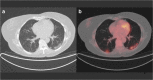

Methods: During the period of maximum incidence of the global pandemic in one of the most affected regions of Spain, there were 145 patients that met inclusion and exclusion criteria and were included in the study. Imaging findings previously described such as ground-glass opacities with low [18F]-FDG uptake were considered images suspicious for SARS-CoV-2 infection. Patients with these findings were referred to RT-PCR testing and close follow-up to confirm the presence or absence of COVID-19.

Results: Suspicious lung imaging findings were present in 7 of 145 patients (4.8%). Five of these 7 patients were confirmed as presenting SARS-CoV-2 infection, this is, COVID-19. In the remaining two, it was not possible to confirm the presence of COVID-19 with RT-PCR, although in one of them, PET/CT allowed an early diagnosis of a lung infection related to a bacterial pneumonic infection that was promptly and adequately treated with antibiotics.